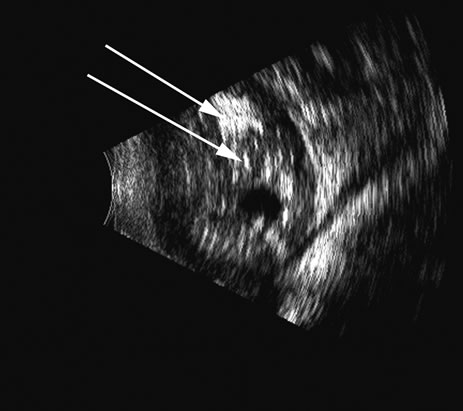

Fig. 20. An eye filled with a retinoblastoma, which has considerable calcium deposits that produce a very reflective, high-amplitude echogenic structure (arrows).